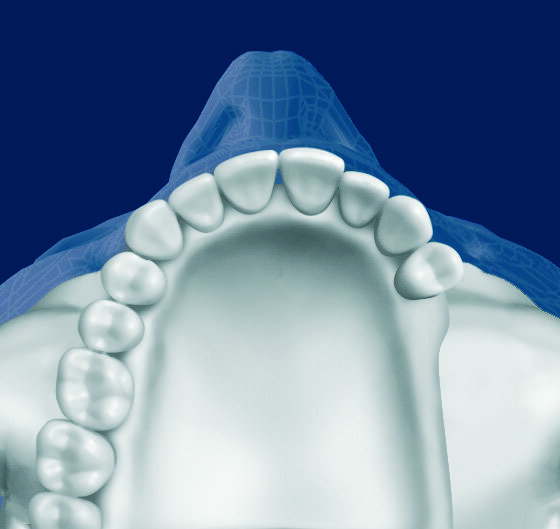

_Ceratura diagnostica virtuale

Utilizzando un software di pianificazione implantare possiamo andare a creare una ceratura diagnostica virtuale che rispetti i parametri sopracitati ovvero lunghezza A-C degli elementi dentali non superiore a più del 20% (solitamente 1,5-2 mm) rispetto agli elementi protesici controlaterali se presenti oppure rispetto alle dimensioni canoniche. È infine possibile importare anche una ceratura diagnostica virtuale realizzata ad hoc dall’odontotecnico (Figg. 4, 5).